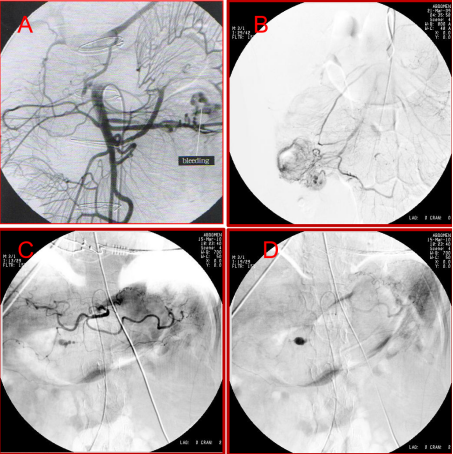

典型病例展示

★ 病例1:十二指肠溃疡出血:超选造影发现外溢,弹簧圈联合微球栓塞成功止血

★ 病例2:十二指肠球部溃疡伴出血

★ 病例3:结肠出血点栓塞

图:胆囊结石、胆总管结石术后 1 个月呕血及黑便;血管造影肝右动脉假性动脉瘤

图:肝门胆管癌PTCD 、胆道支架术后 3 天,引流管反复引出血性胆汁;肝动脉造影未见异常,导丝交换撤出引流管后再次行肝动脉造影,对比剂经引流道外溢至腹腔。

图:造影见胃十二指肠动脉近段动脉瘤,并可见造影剂溢出;弹簧圈栓塞后动脉瘤闭塞。

图:胰十二指肠切除术后11天出现便血和黑便;肠系膜上动脉造影见分支动脉假性动脉瘤。